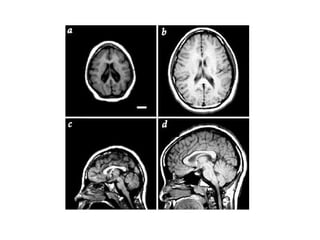

ESTUDIOS EN HUMANOS C.PF. Es la última en madurar La materia gris cae y la blanca aumenta por mielinización =sube conducción y comunicación Aumenta control cognitivo Ganglios basales y C.PF. relacionados con suprimir respuestas inapropiadas y suprimir estímulos irrelevantes

ESTUDIOS EN HUMANOSC.PF. Es la última en madurar La materia gris cae y la blanca aumenta por mielinización =sube conducción y comunicación Aumenta control cognitivo Ganglios basales y C.PF. relacionados con suprimir respuestas inapropiadas y suprimir estímulos irrelevantes